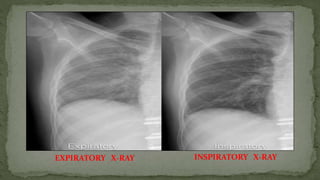

F. Inspiration (Degree of inspiration)

 To judge the degree of inspiration, count the number of ribs above the

diaphragm.

 The midpoint of the right hemi-diaphragm should be between the 5th and 7th

ribs anteriorly.

 The anterior end of the 6th rib should be above the diaphragm as should the

posterior end of the 10th rib.

 If more ribs are visible the patient is hyperinflated

 If fewer it indicates inadequate inspiration

 Poor inspiration will make the heart look larger, give appearance of basal

shadowing and cause the trachea to appear deviated to the right

EXPIRATORY X-RAY INSPIRATORY X-RAY